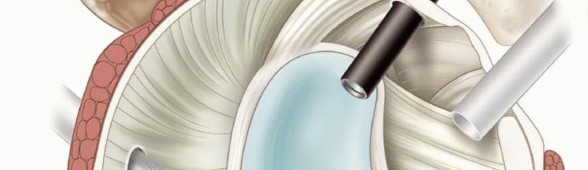

Illustration of inferior glenohumeral ligament - Dr. Mohammed Hutaif

Image

The capsuloligamentous structures serve as the primary static restraints of the shoulder. The most critical of these is the Inferior Glenohumeral Ligament (IGHL) complex. Composed of a distinct anterior band, a posterior band, and an intervening axillary pouch, the IGHL functions as a reciprocal hammock. In the provocative position of abduction and external rotation, the anterior band becomes taut, acting as the primary restraint to anterior translation.